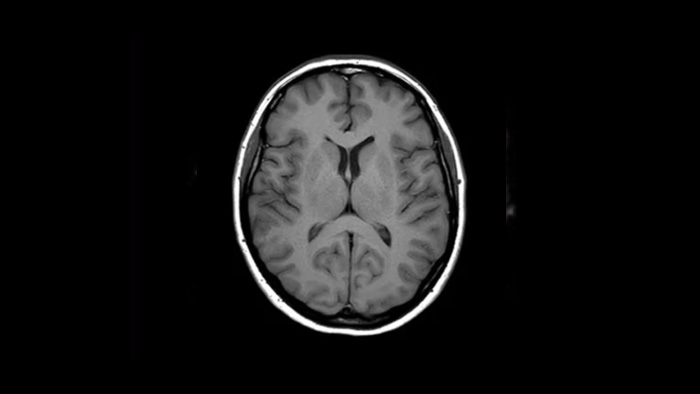

Pewność diagnostyczna Poszerz swoje możliwości obrazowania we wszystkich obszarach klinicznych. Zobacz, jakie korzyści odnoszą inni przedstawiciele Twojej branży.

Dowiedz się, jak w MCVI [Michigan CardioVascular Institute] poprawiła się jakość badań rezonansem magnetycznym.